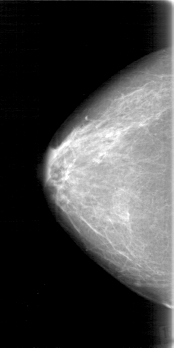

D_4024_1.RIGHT_CC

RIGHT_CC LINES 5206 PIXELS_PER_LINE 2596 BITS_PER_PIXEL 12 RESOLUTION 43.5 NON_OVERLAY